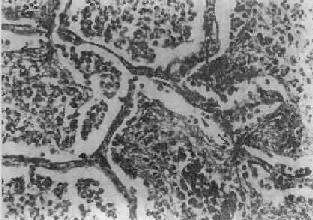

二、肺炎肺炎(pneumonia)通常是指肺的急性渗出性炎症,为呼吸系统的多发病、常见病。据世界卫生组织调查,肺炎死亡率占呼吸系统急性感染死亡率的75%。在我国,各种致死病因中,肺炎占第5位。肺炎可由不同的致病因子引起,根据病因可将肺炎分为感染性(如细菌性、病毒性、支原体性、真菌性和寄生虫性)肺炎,理化性(如放谢性、吸入性的类脂性)肺炎以及变态反应性(如过敏性和风湿性)肺炎。由于致病因子和机体反应性的不同,炎症发生的部位、累及范围和病变性质也往往不同。炎症发生于肺泡内者称肺泡性肺炎(大多数肺炎为肺泡性),累及肺间质者称间质性肺炎。病变范围以肺小叶为单位者称小叶性肺炎,累及肺段者称节段性肺炎,波及整个或多个大叶者称大叶性肺炎。按病变性质可分为浆液性、纤维素性、化脓性、出血性、干酪性、肉芽肿性或机化性肺炎等不同类型。 (一)细菌性肺炎 1.大叶性肺炎 大叶性肺炎(lobar pneumonia)主要是由肺炎链球菌感染引起,病变起始于肺泡,并迅速扩展至整个或多个大叶的肺的纤维素性炎。多见于青壮年,临床表现为骤然起病、寒战高烧、胸痛、咳嗽、吐铁锈色痰、呼吸困难,并有肺实变体征及白细胞增高等。大约经5~10天,体温下降,症状消退。 【病因和发病机制】 95%以上的大叶性肺炎由肺炎链球菌引起,尤以Ⅲ型者毒力最强。此外,肺炎杆菌、金黄色葡萄球菌、溶血性链球菌、流感嗜血杆菌也可引起。受寒、疲劳、醉酒、感冒、麻醉、糖尿病、肝、肾疾病等均可为肺炎的诱因。此时,呼吸道的防御功能被削弱,机体抵抗力降低,易发生细菌感染。细菌侵入肺泡后在其中繁殖,特别是形成的浆液性渗出物又有利于细菌繁殖,并使细菌通过肺泡间孔或呼吸细支气管迅速向邻近肺组织蔓延,从而波及整个大叶,在大叶之间的蔓延则系带菌渗出液经叶支气管播散所致。 【病理变化】 病变一般发生在单侧肺,多见于左肺下叶,也可同时或先后发生于两个以上肺叶。病变基本特征是肺的微循环障碍。由于毛细血管通透性增高,大量纤维蛋白原渗出于肺泡,使肺组织大面积广泛实变。病变早期,肺叶充血、水肿,肺泡腔内有大量浆液性渗出物,混有少数红细胞、中性粒细胞和巨噬细胞,并含有大量细菌。1~2天后,即有大量纤维蛋白原渗出,肺泡腔内充满混有红细胞、中性粒细胞、巨噬细胞的纤维素性渗出物,纤维素丝可穿过肺泡间孔与相邻肺泡中的纤维素网相连(图9-15)。病变肺叶质实如肝,明显肿胀,重量增加,呈灰白色(图9-16)。如血管损伤较重、出血较多,外观可呈红色。大约经5~10天,炎症消退,细菌被吞噬细胞吞噬清除,渗出物被溶解,或经淋巴管吸收或被咳出。大叶性肺炎时,肺组织常无坏死,肺泡壁结构也未遭破坏,愈复后,肺组织可完全恢复其正常结构和功能。

图9-15 大叶性肺炎 肺泡腔内充满纤维素性渗出物,纤维素丝穿过肺泡间孔,使相邻肺泡内的纤维素网互相连接